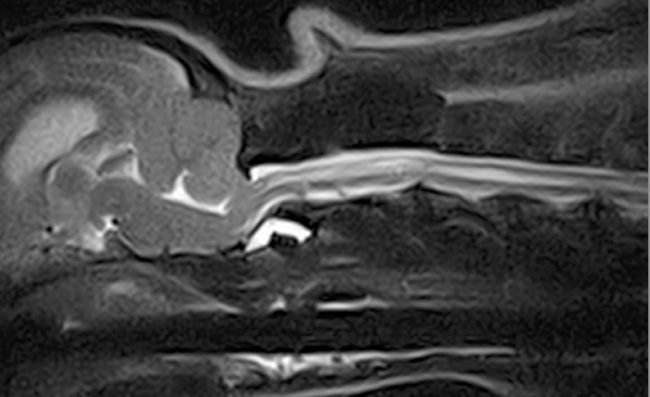

Le diagnostic des dermatophytoses repose sur la culture fongique, mais ses résultats sont parfois longs, trop longs à obtenir. Or il existe de nombreuses techniques permettant d’effectuant le diagnostic immédiatement au chevet du patient : lampe de Wood, cytologie (scotch ou impression directe), et trichogramme Une étude récente sur 30 chiens et 15 chats a…